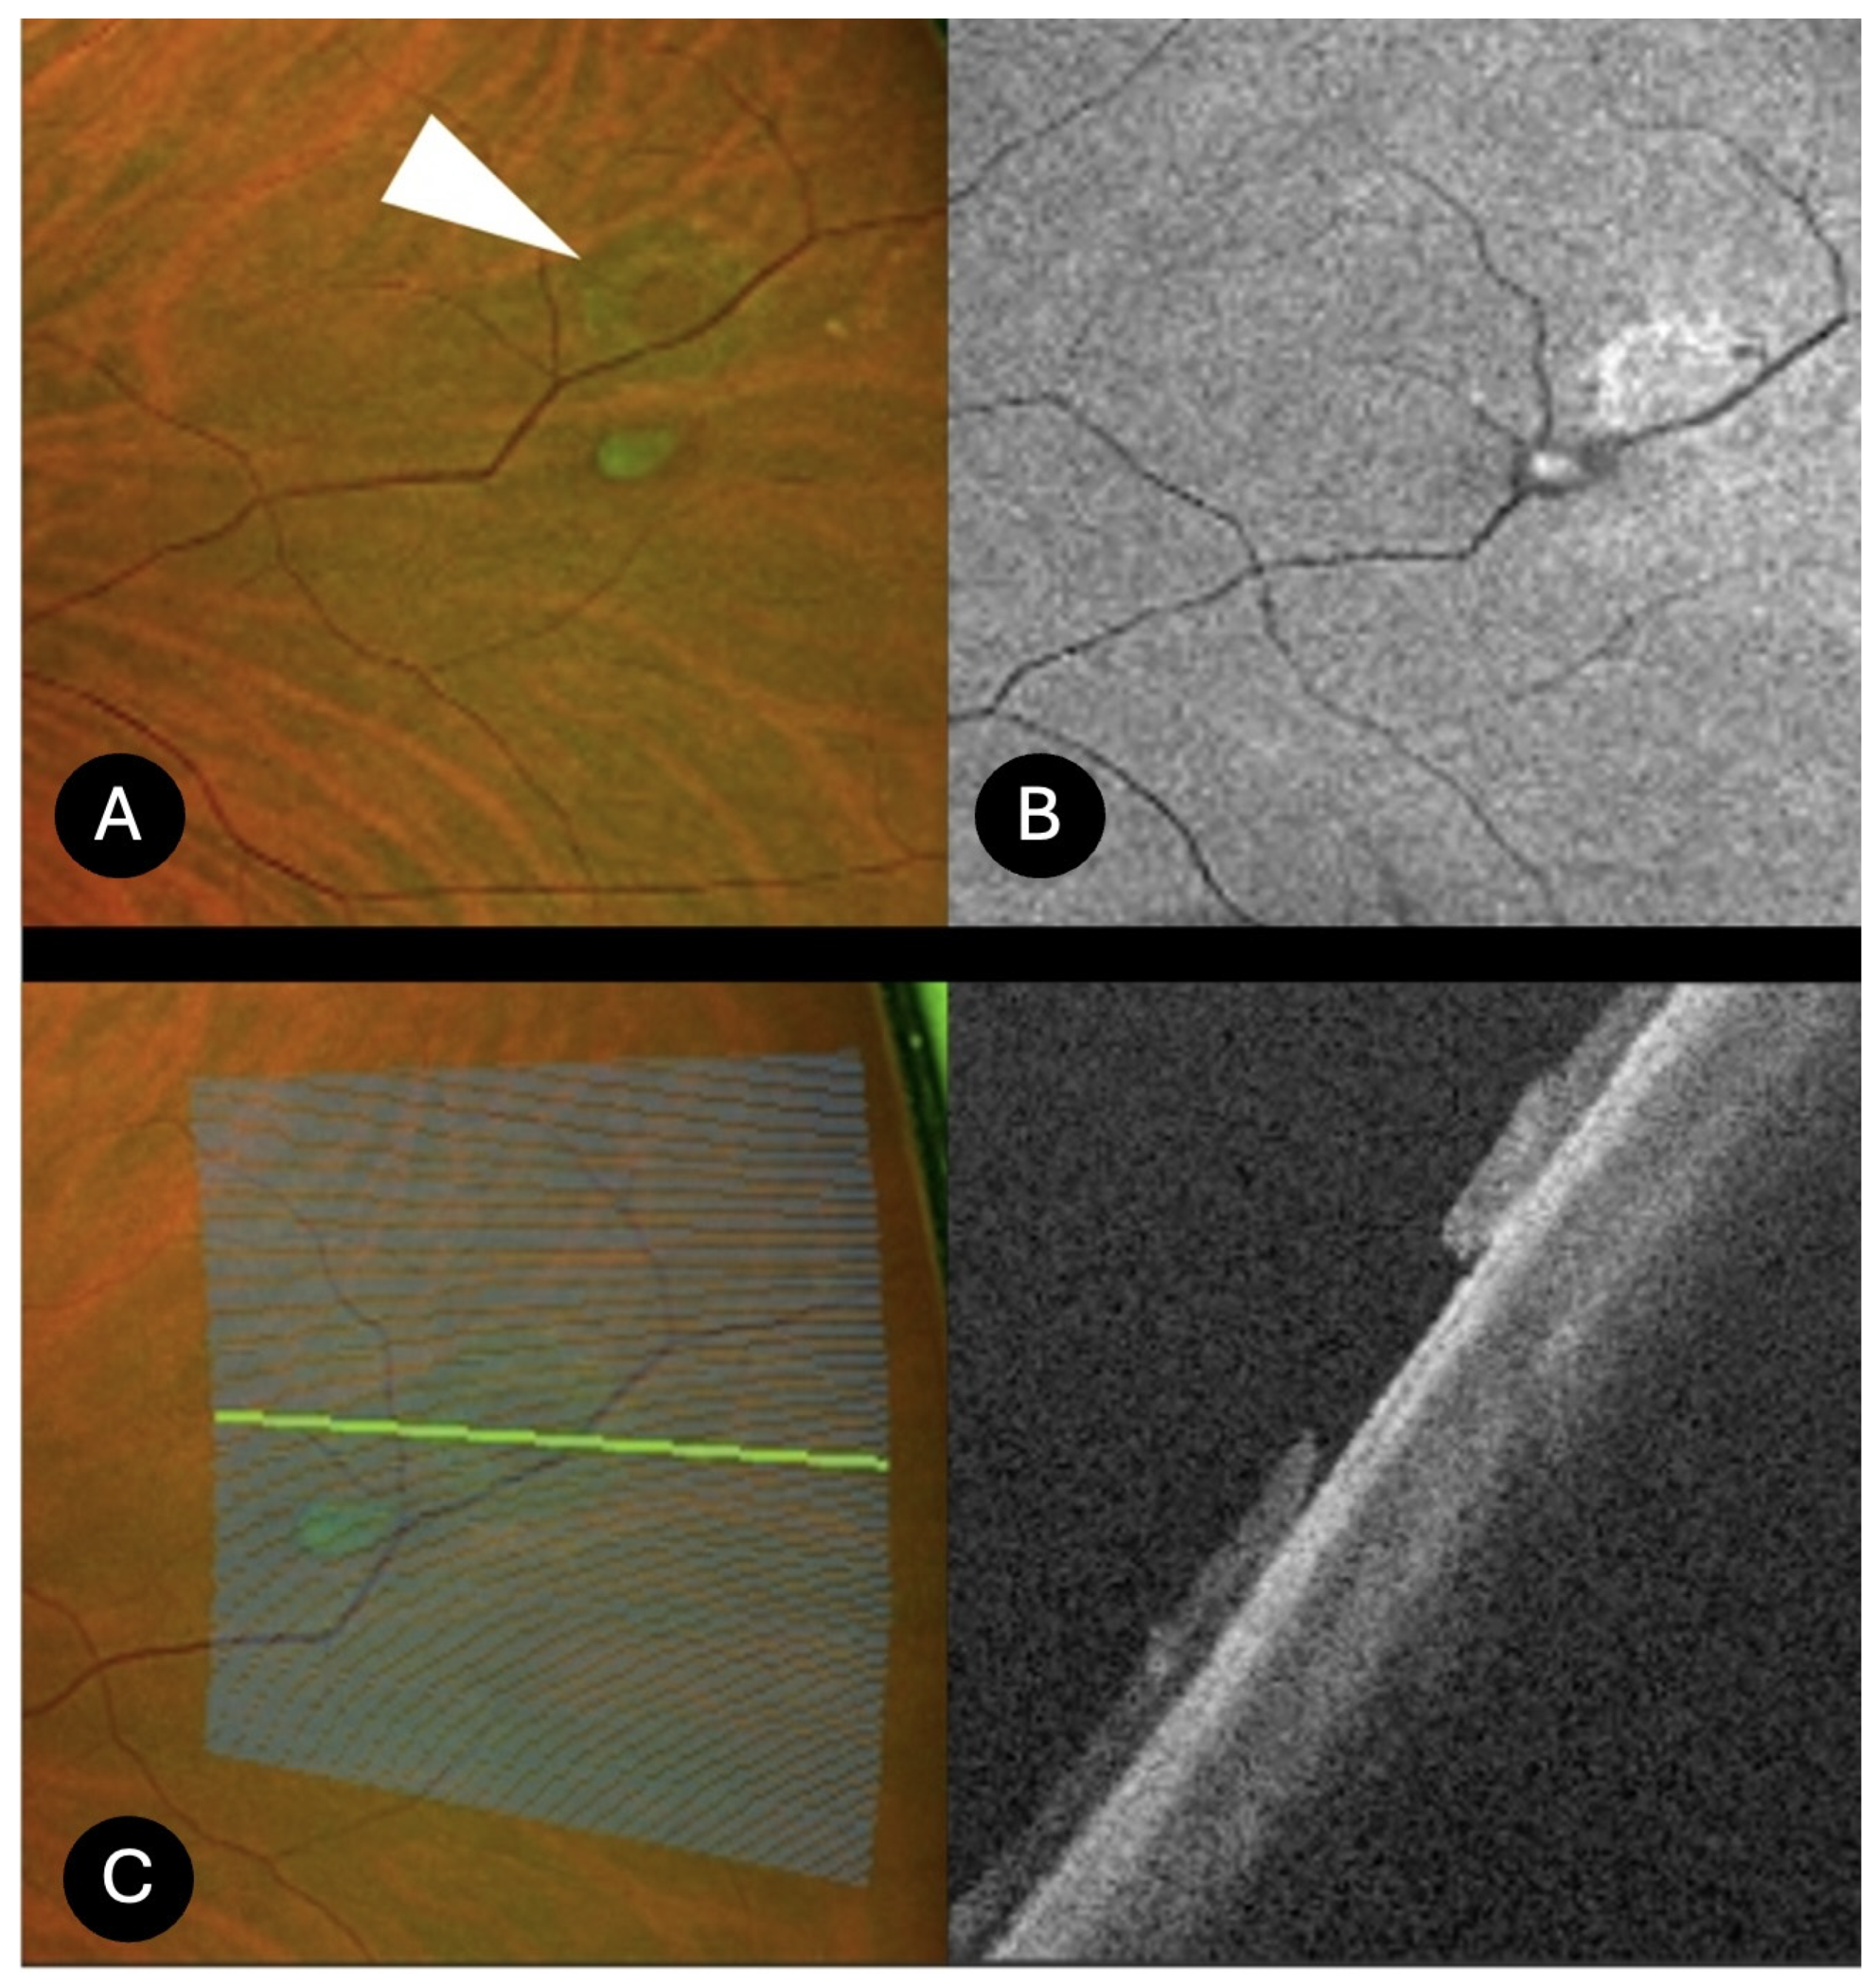

- Lattice degeneration (N = 25)